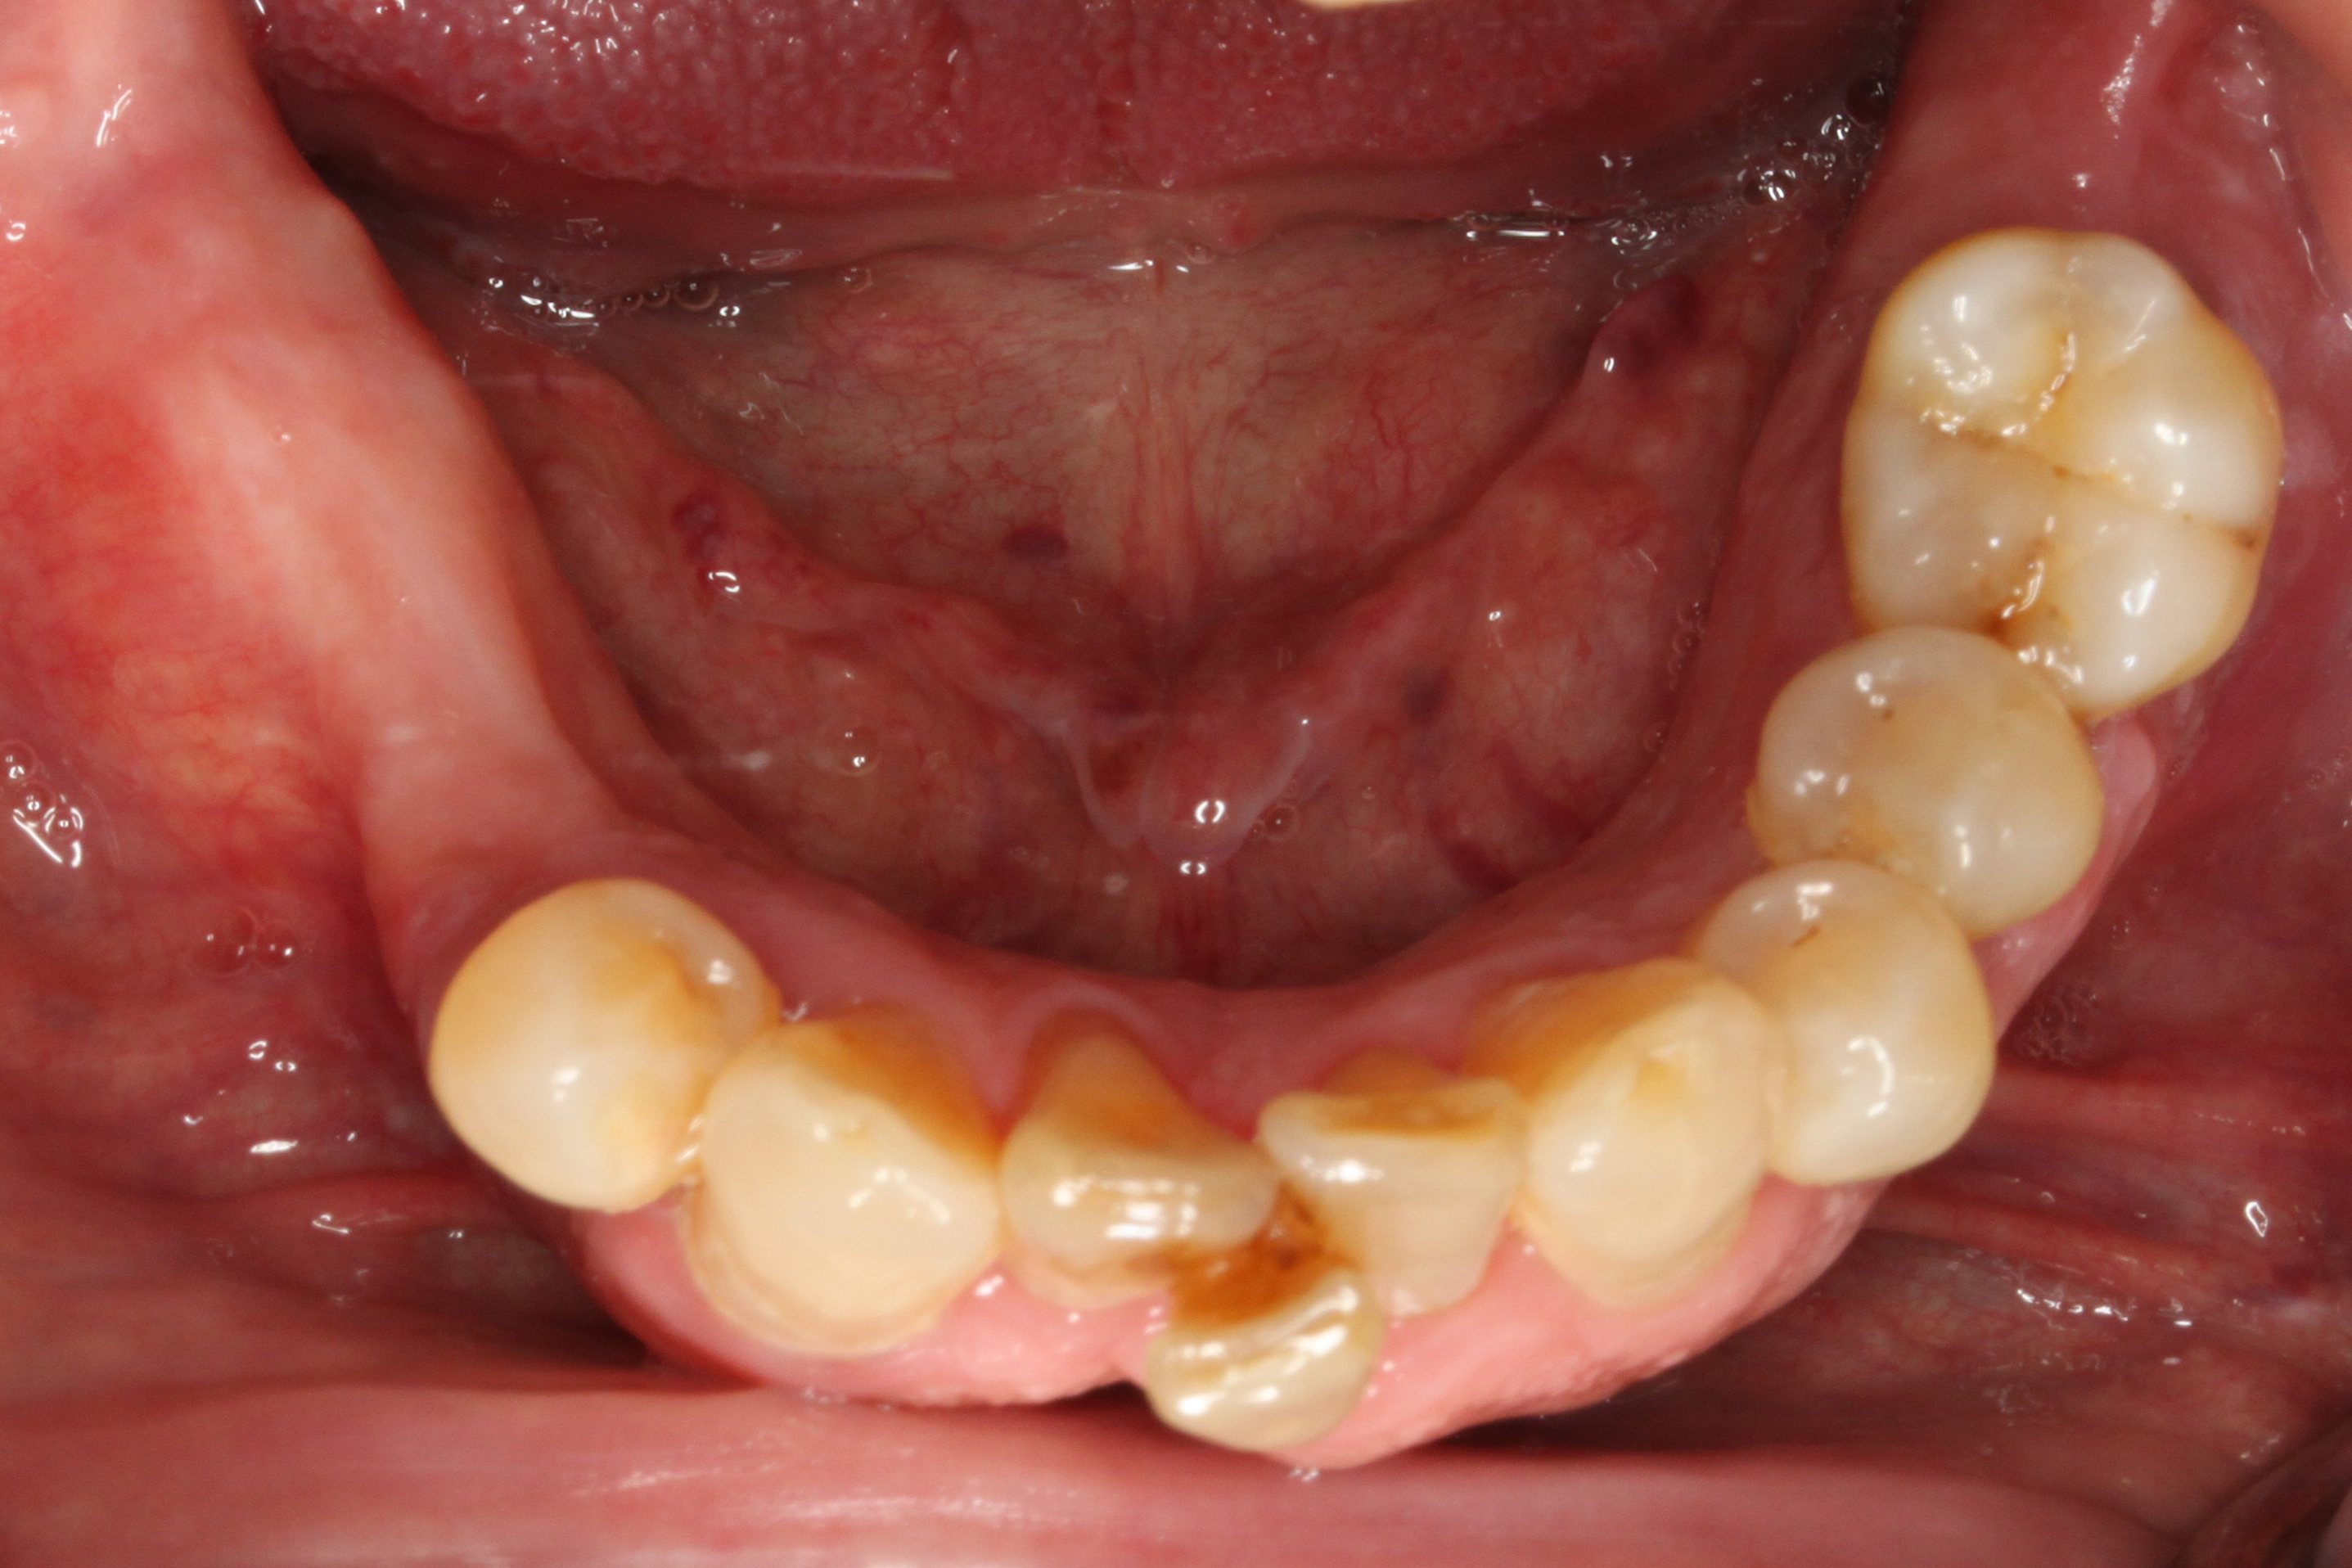

Fig 6. A 45-year-old man presented with a failing dentition requesting full-arch replacement.

Figure 6